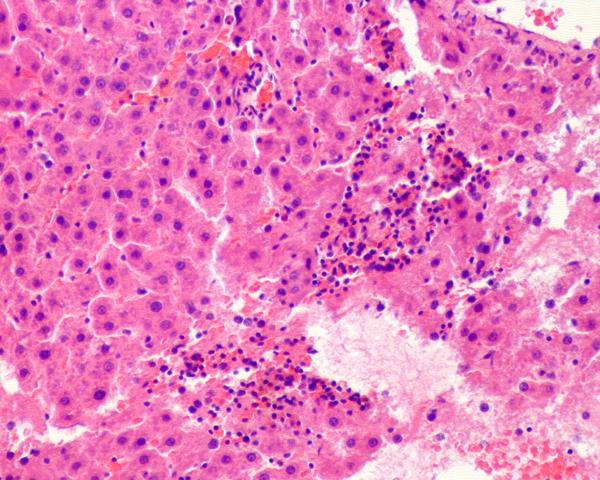

求解病理图片